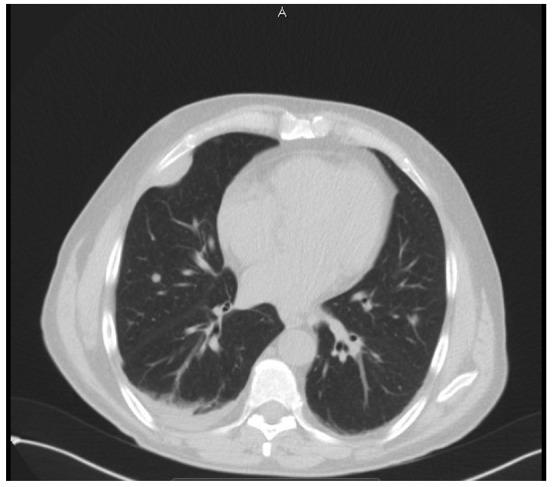

Angiosarcoma is an extremely rare, high-grade malignancy, which accounts for <2% of all soft-tissue sarcomas. Cases of primary renal angiosarcoma represent 1% of these. Angiosarcomas involving the kidney usually originate from metastatic skin lesions or primary visceral lesions and most often occur in the sixth and seventh decades of life. The present study describes a case of primary renal angiosarcoma that presented as a large right-sided renal mass with symptoms of flank pain. Despite surgical removal of the tumor, recurrent disease with associated lung metastases was identified at the surgical site following adjuvant chemotherapy. The patient succumbed to the disease 13 months after the diagnosis.

血管肉瘤是一种极其罕见的高级别恶性肿瘤,占所有软组织肉瘤的比例不到2%。原发性肾血管肉瘤病例占其中的1%。累及肾脏的血管肉瘤通常起源于转移性皮肤病变或原发性内脏病变,最常发生在60和70岁年龄段。本研究描述了一例原发性肾血管肉瘤病例,该病例表现为右侧肾脏巨大肿块并伴有胁腹疼痛症状。尽管手术切除了肿瘤,但辅助化疗后在手术部位发现了伴有肺转移的复发性疾病。患者在诊断后13个月死于该疾病。